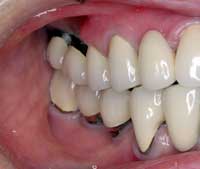

| Before | After |